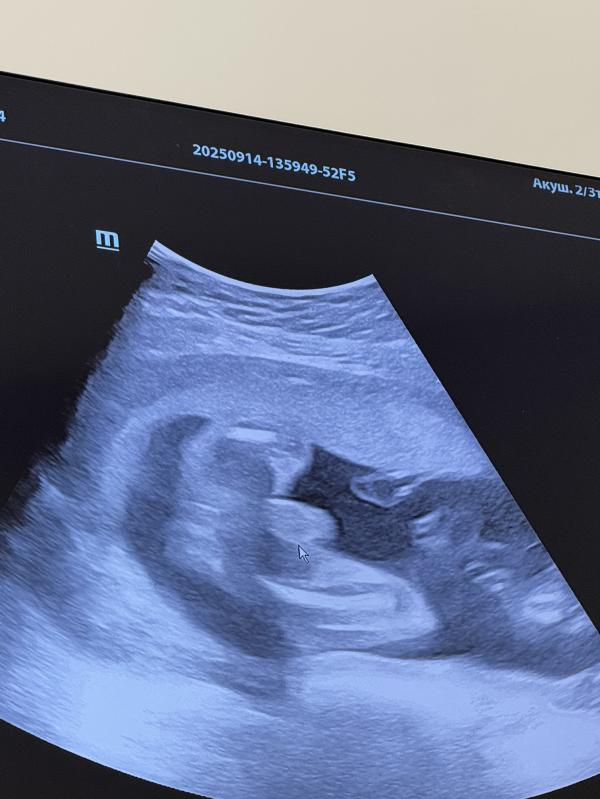

Себе на память 💙

Вчера была на узи

Решила провериться после простуды на всякий случай,

АльхамдуЛлилях все хорошо с малышом

Показал свои причиндалы🤭Чтобы точно убедились,что мальчик))

Там Где стрелка,там машонка

Вес 700 гр

23,6 дней

Воды в норме

Плацента 2 степени зрелости

Шейка 40мм

Зев закрыт